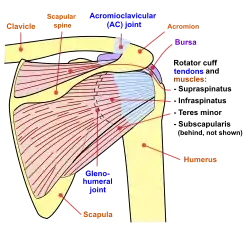

Diagram of the human shoulder joint, front view Diagram of the human shoulder joint, back view

Diagram of the human shoulder joint, back view The left shoulder and acromioclavicular joints, and the proper ligaments of the scapula